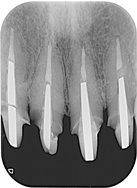

治療前,X光片及口內照片。

右上側門牙及左上正中門牙斷裂。